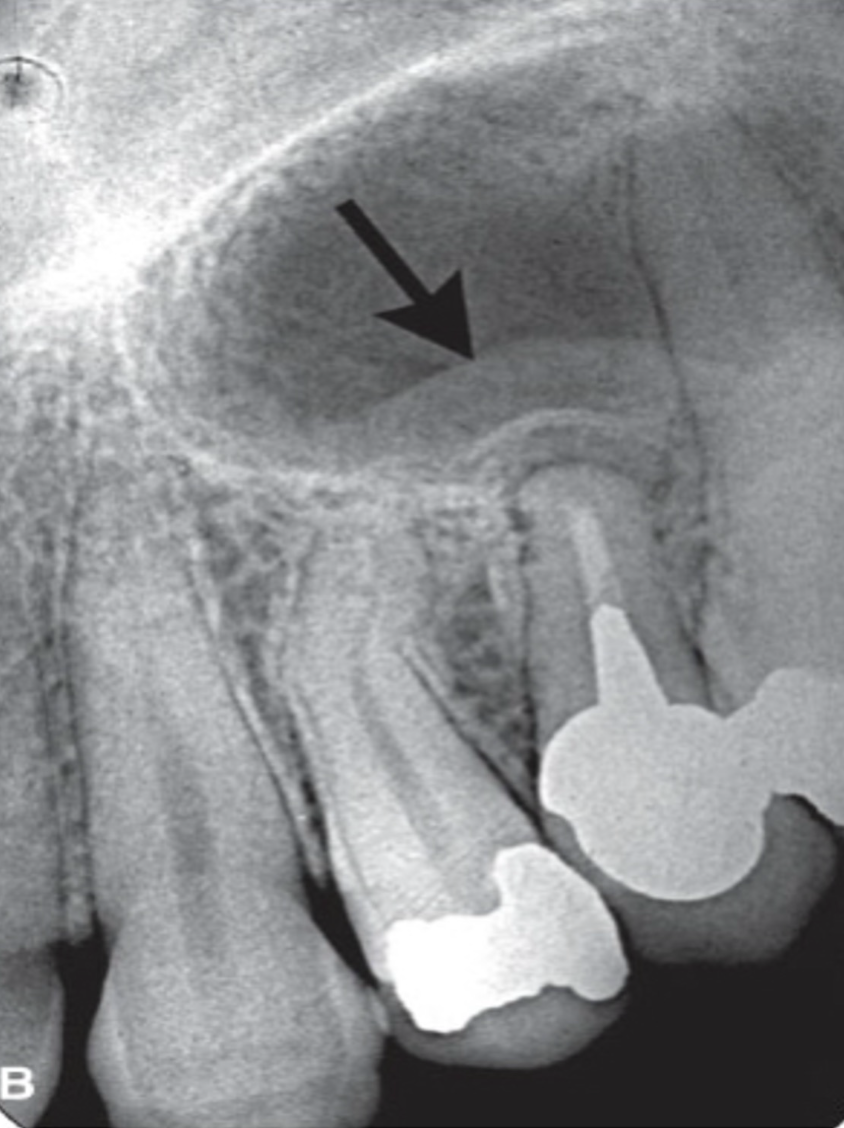

different radiographic presentations of apical periodontitis

reactive changes → remodeling of floor of maxillary sinus, with maxillary sinus mucosal thickening

long-standing lesions → radiolucency at root apex with surrounding radiopacity

imaging appearance varies on disease stage and bone response

location → mostly apical, but can be accessory canals or root perforations and fractures